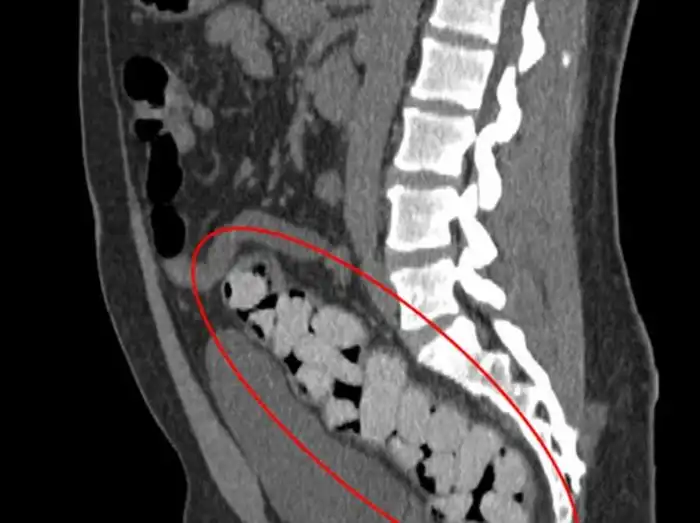

Девять пакетов кокаина

Эти цветные пакетики наркотиков находятся в толстой кишке